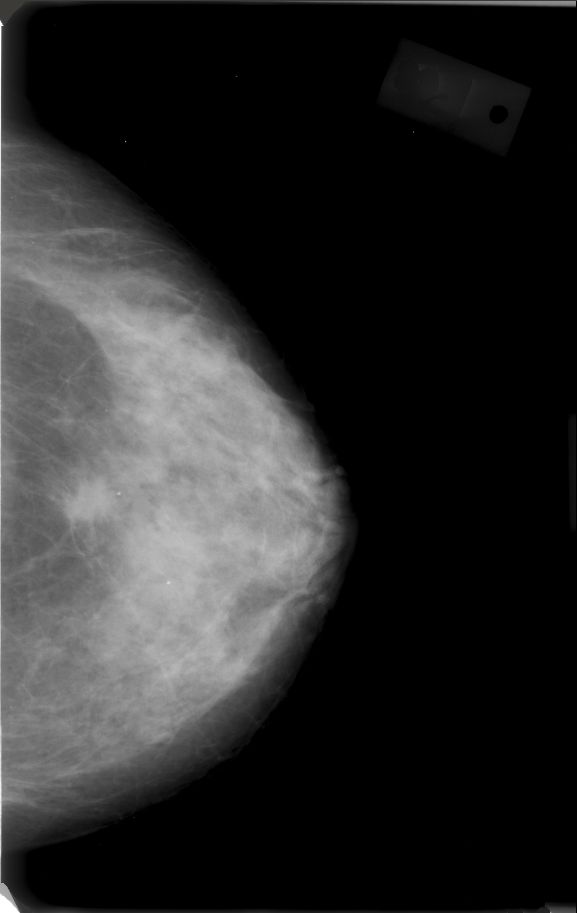

- python - remove pixel annotations in dicom image - Stack Overflow